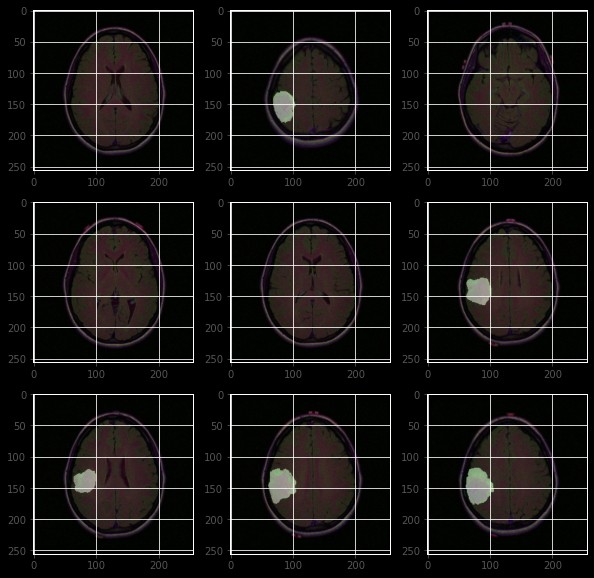

注意,这里的输入大小是256x256的单通道图像(灰度图),输出是同样大小的单通道图像,表示分割结果。编码器部分负责提取图像的特征,而解码器部分则负责将提取的特征还原为分割结果。通过合理的预处理和模型训练,我们可以得到不错的分割结果。当然,实际应用中可能还需要考虑更多的细节,比如数据增强、模型调参等。Unet模型在图像分割领域可是个老熟人了,尤其是在医学图像处理上,表现相当出色。我们先来看看Une